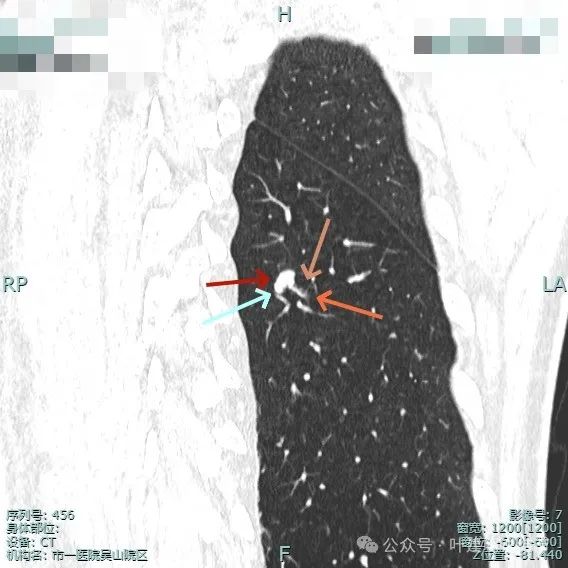

病灶表面细锯齿状,整体膨胀性明显,血管进入并异常增粗,整体轮廓清,周围肺野清晰。

病灶表面不平,形态略不规则,血管进入,边缘细锯齿状。